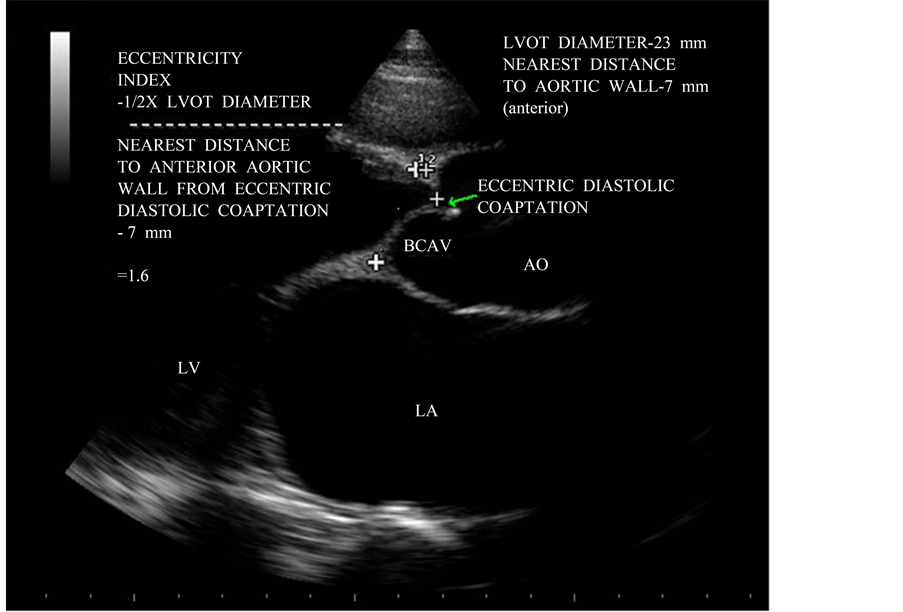

Figure 8. Parasternal long axis view showing the “eccentricity index”.

Demonstration of marked eccentricity of the aortic valve diastolic echoes with respect to the aortic lumen appears to be the hallmark of a congenital bicuspid aortic valve. A normal tricuspid aortic valve, on the other hand, closes without cusp folding and therefore does not produce multiple diastolic echo sources along the lines of closure and the diastolic positions of cusp echoes is near the middle of the aortic lumen. In the case of the bicuspid aortic valve, the aortic valve diastolic position would be consistently observed near the anterior or near the posterior aortic margin depending on the location of the dominant leaflet. The eccentricity index denotes the deviation of the diastolic cusp position from the middle of the aortic lumen and takes into account the internal diameter of the aortic root. The index would equal unity if the valve cusps closed exactly in the center of the aortic root, while very high values (3.5 or above) would indicate extreme asymmetry of the cusp images. The eccentricity index was low, ranging from 1.0 to 1.25 in normal tricuspid aortic valve and high (1.5 to 5.6) in all patients with bicuspid aortic valve. The eccentricity index is 1.6 in this patient as shown in Figure 8 revealed the acquired rheumatic etiology for the bicuspid appearance in parasternal long axis view.